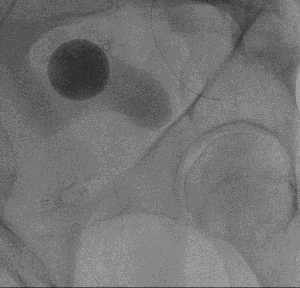

picture 2Overall, the procedure involves shrinking the prostate by treating its blood vessels. An interventional radiologist gains access through a small incision in the upper thigh or the wrist. From there, small particles are injected into the prostate to slow the blood flow to the gland, causing the prostate to shrink. Relief from BPH symptoms occurs in the following weeks and months. It is a relatively painless procedure using conscious sedation. After the procedure, UCSF Radiology follows up with patients at one, six and 12 months.